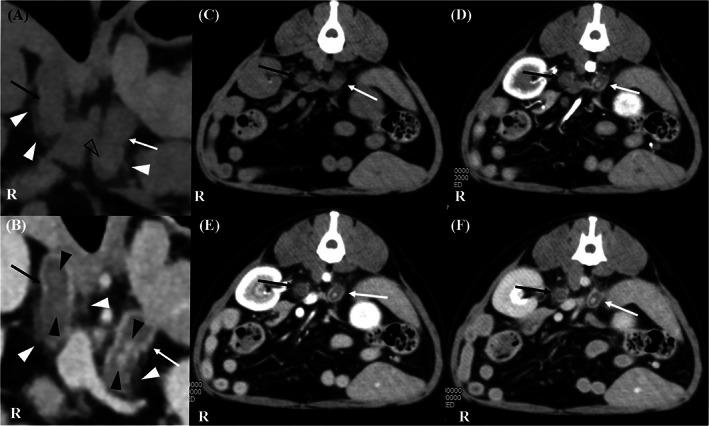

Nontraumatic adrenal hemorrhage (NTAH) has been associated with stress-induced catecholamines release in underlying conditions such as sepsis and recent surgery in humans. It can lead to primary hypoadrenocorticism (HOAC) when both adrenal glands are involved, with nonspecific clinical signs and laboratory findings that can lead to a missed diagnosis. Bilateral thickening of the adrenal glands with periadrenal fat stranding was identified in a 10-year-old male Maltese dog after abdominal surgery. The dog showed clinical signs and biochemical changes consistent with HOAC, but treatment for presumed critical illness-related corticosteroid insufficiency was initiated. Clinical signs relapsed with a 3-week dose reduction of hydrocortisone, and a reduction in adrenal size was observed on follow-up ultrasound examination. Hormonal testing confirmed HOAC in the dog. To the best of our knowledge, HOAC caused by spontaneous NTAH has not been reported in the veterinary literature. This report describes a dog that developed HOAC with presumed adrenal atrophy after suspected spontaneous bilateral NTAH.

非创伤性肾上腺出血(NTAH)与人类潜在疾病中的应激诱导儿茶酚胺释放有关,如败血症和近期手术。当双侧肾上腺均受累时,可导致原发性肾上腺皮质功能减退症(HOAC),其无特异性的临床症状和实验室发现可能导致漏诊。一只 10 岁雄性马耳他犬在腹部手术后,发现双侧肾上腺增厚伴肾上腺周围脂肪条索状。该犬表现出与 HOAC 一致的临床症状和生化变化,但开始治疗疑似与危重病相关的皮质激素不足。在氢化可的松剂量减少 3 周后,临床症状复发,随后在超声检查中观察到肾上腺缩小。激素检测证实该犬存在 HOAC。据我们所知,兽医文献中尚未报道过自发性 NTAH 引起的 HOAC。本报告描述了一例疑似自发性双侧 NTAH 后发生 HOAC 并伴有肾上腺萎缩的犬。